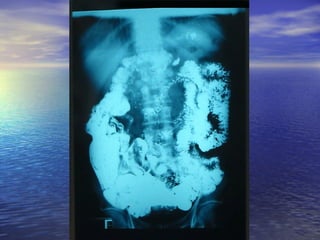

• 1.- CALIBRE: Dilución = obstrucción1.- CALIBRE: Dilución = obstrucción distal, enf.distal, enf.

Celiaca,Celiaca, whipple, linfosarcomawhipple, linfosarcoma

• 2.- ESTENOSIS: Enf. De Crohn, linfosarcoma,2.- ESTENOSIS: Enf. De Crohn, linfosarcoma,

tuberculosis, invasión por tumores cercanostuberculosis, invasión por tumores cercanos

del páncreas, colon.del páncreas, colon.

• 3.- DEFECTOS DE LLENADO: Pólipos ,Sx. Peutz-3.- DEFECTOS DE LLENADO: Pólipos ,Sx. Peutz-

Jegher,Jegher, poliposis familiar, enf. De Crohn, linfomas ypoliposis familiar, enf. De Crohn, linfomas y

metástasis.metástasis.

• 4.- DIVERTICULOSIS: Diverticulosis yeyunal, pseudo-4.- DIVERTICULOSIS: Diverticulosis yeyunal, pseudo-

divertículos (Crohn, esclerosis sistémica)divertículos (Crohn, esclerosis sistémica)

5.- FÍSTULAS: Enf. De Crohn, tumores5.- FÍSTULAS: Enf. De Crohn, tumores

malignos y postoperatoriosmalignos y postoperatorios

6.- ANORMALIDADES EXTRÍNSECAS:6.- ANORMALIDADES EXTRÍNSECAS:

Metástasis , serosa, ascitis, lesionesMetástasis , serosa, ascitis, lesiones

inflamatorias o neoplasias cercanas.inflamatorias o neoplasias cercanas.

7.- DILUCIÓN DEL MEDIO DE7.- DILUCIÓN DEL MEDIO DE

CONTRASTE: Lesiones proximales uCONTRASTE: Lesiones proximales u

obstructivas, Sx. De Zollinger Ellison.obstructivas, Sx. De Zollinger Ellison.